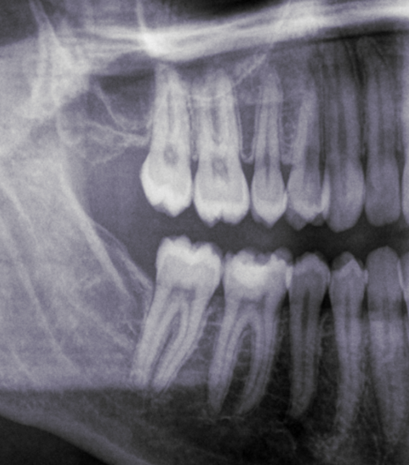

Look at these x-rays:

This patient was a female in her mid-30s. We will call her FA. As you can see, she only keeps her left wisdom teeth. At the age of 15, FAâs dentist wrongly diagnosed all her four wisdom teeth as impacted and recommended her to get them all out. FA was scheduled for two appointments: one to remove her right ones, and the other for the left ones.

Her left wisdom teeth, also diagnosed as impacted back then, are obviously not impacted! Having examined her mouth, I can confirm they are perfect, ideally erupted and taking part in chewing like the normal teeth they are. Yet, they were diagnosed as impacted, with no place and problematic. This is nothing short of horrifying.

And I can very confidently say that her right molars were not impacted either, because of her wide retromolar spaces to the right (that is, the spaces behind her second molars), because we can be sure that her dentist was not able to properly diagnose impactions, and because of how ideally positioned and erupted her remaining wisdom teeth are. And no, she wasnât having any kind of symptoms, discomfort or infections. Nor did she need the removal for any orthodontic or surgical reasons.